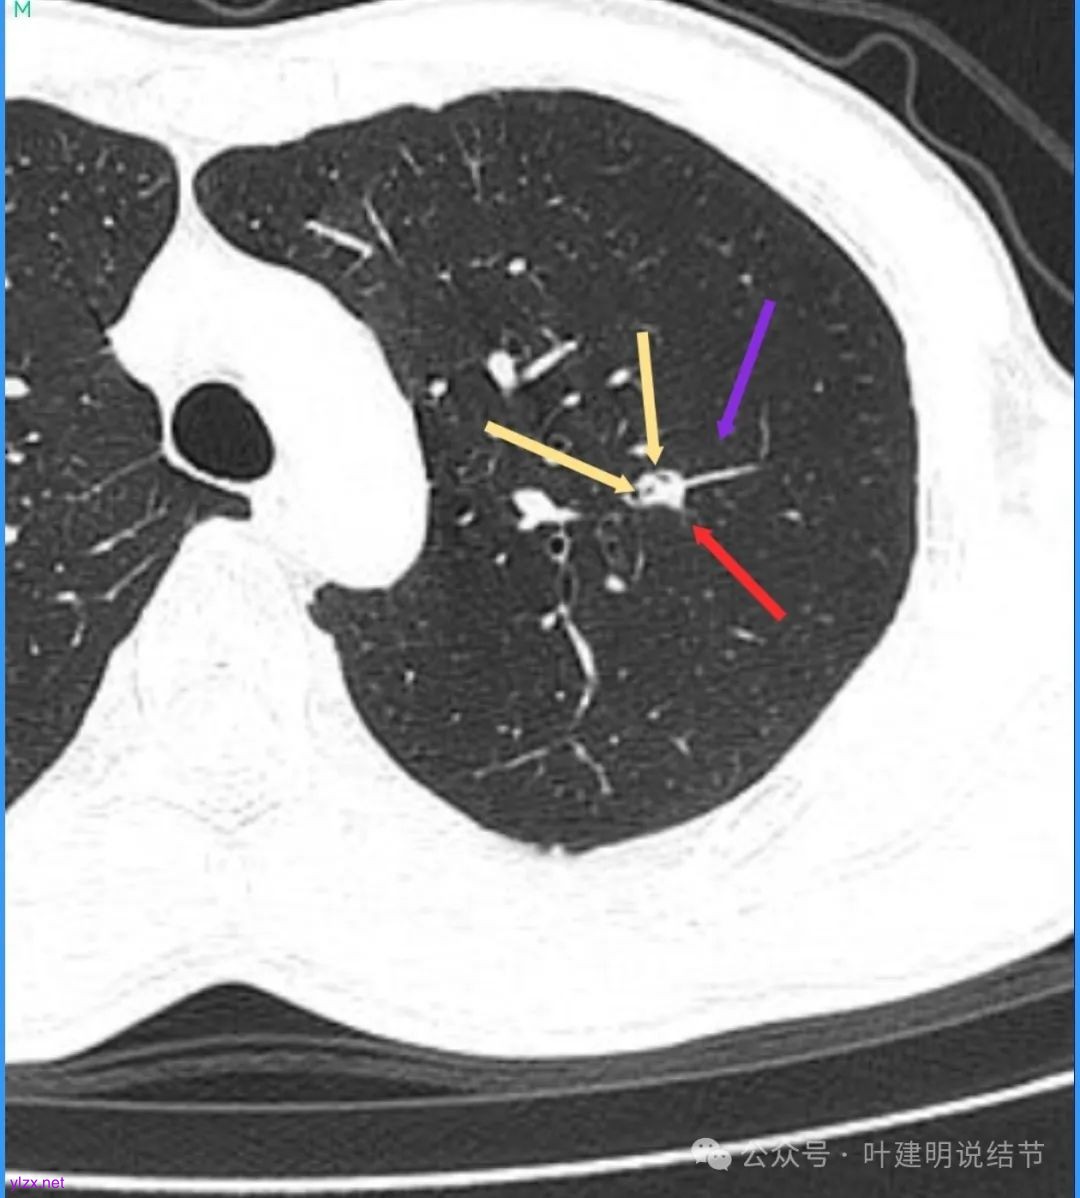

再看看近半年前2024年11月时的影像:

我们发现一是病灶与25年3月的几乎没有区别,二是原来蓝色箭头处不太像血管,而是结节边缘的一部分,而结节灶内又是有扩张支气管的。

左肺上叶这个病灶总体上来讲2025年3月的与2024年11月份相比没有显著进展。我们逐层从细节上去分析,会发现:1、病灶开始出现的层面就有临近的支气管扭曲变形,这些人用肿瘤导致的牵拉不能解释,反而用细支气管扩张伴慢性炎容易解释;2、病灶内部仍然多个层面都有见到扩张的细支气管,可是如果是肿瘤,与导致细支气管扩张相应的病灶本身的收缩力或者边缘毛刺又不明显;3、病灶边缘基本上都比较光滑平直,没有像外周浸润性生长的枫叶或者毛刺;4、虽然有血管贴边或者进入,但是说不上显著的血管异常增粗;5、整体来讲病灶实性成分密度过高,随访对比进展不明显,用结节是恶性不太能够解释相应的影像表现,所以我倾向于考虑是细支气管扩张伴有周围慢性炎或者肉芽肿性炎。至少从风险高低的角度来看,几个月的间隔没有明显进展的情况下加上位置又不好,如果手术需要切除范围比较多,所以应该在随访观察比较稳妥,可以考虑半年复查对比。意见供参考!